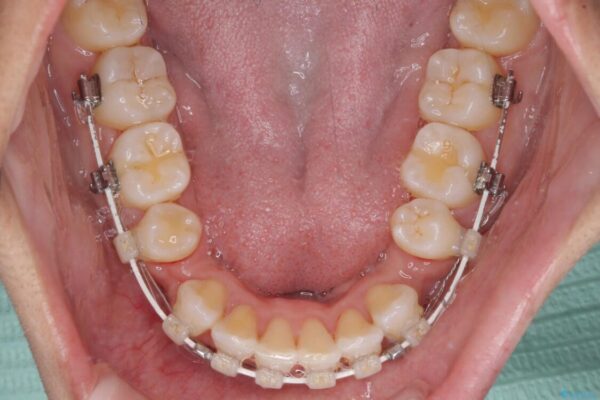

治療後

• 抜歯矯正で唇を閉じやすく 目立たないワイヤー装置 治療後画像